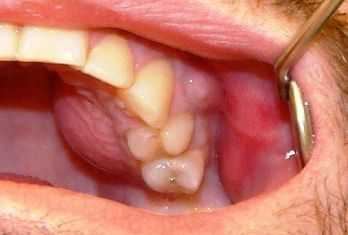

После острой стадии наступает подострая. На десне образуется гнойничок или свищ, через который гнойные выделения и воспалительная жидкость выходят наружу.

![Свищ на десне]()

Затем боль утихает, но очаг инфекции остаётся, поэтому сохраняется высокая температура и нарастает слабость. Если в этот период не обратиться к врачу, то инфекция распространится по всему организму и человек может погибнуть.